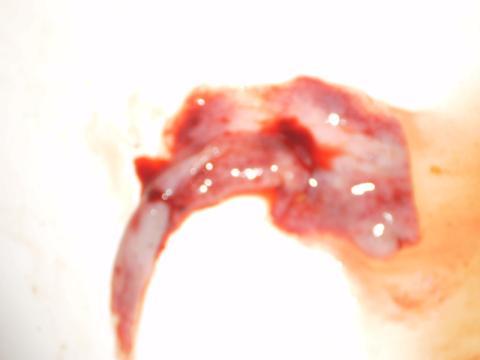

Pro větší náhled klikněte na obrázek

Dobrý den,chtěla bych se vás zeptat mám problém už asi půl roku že po styku nebo při styku krvácím nkdy jen trochu jindy jen jakoby špinění ale dříve jsem problém neměla. další vě je že před časem ze mě vyšlo něco ( přikládám foto ) abych zjistila co to je je to už asi tak rok a něco myslela jsem tehdy, že jsem samovolně potratila na gyndě jsem byla ale foto jsem tam neukazovala. ted jsem asi rok na gyndě nebyla protože jsem v cizině. dneska při menstruai zas se mě vyšel kus něčeho co bych popsala stejně jakoněco jako co je na te foto ale menšího. Začínám se bát zda to nejsou nějaké cysty. Prosím naléhavě o odpověd. děkuji

Bohužiaľ váš problém si vyžaduje vyšetrenie u lekára. Krvácanie alebo špinenie po styku je znakom zápalu v pošve,alebo poranenia krčku, to nám potvrdí alebo vyvráti práve t vyšetrenie. Pokiaľ z vás niečo vypadne a je to mimo menštruáciu a nie je len to krvná zrazenina s prímesou hlienu, tak je nutné vyhľadať lekára a riešiť to s jeho pomocou. takto na diaľku vám bohužiaľ nedokážem pomôcť!